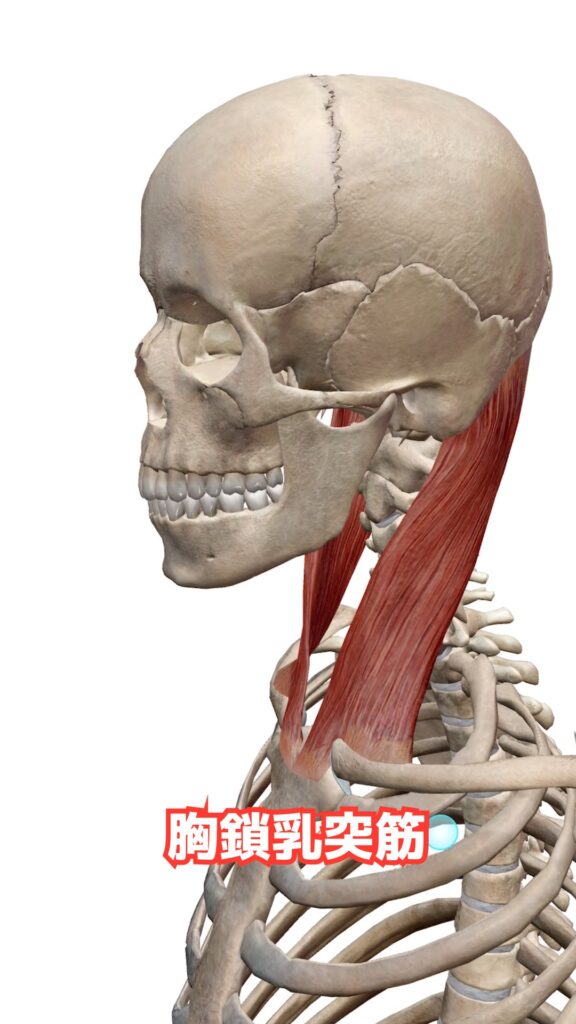

▼ この記事で紹介する胸鎖乳突筋の詳細はこちら

→ 胸鎖乳突筋とは?起始停止・作用を理学療法士が解説

・胸鎖乳突筋

▼ 頭頸部の動きに深く関わる胸鎖乳突筋について詳しく解説!